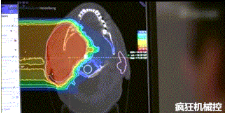

▲360°重離子治療一體機治療腫瘤

360°重離子治療一體可從任何角度用重離子(碳,氦,氧)和質(zhì)子(氫)照射腫瘤。此外,基于機器人的治療臺可以通過六種方式進行調(diào)整。

光柵掃描被集成到360°重離子治療一體機中,這種極其精確的照射方法以毫米為單位掃描腫瘤,可以保護健康組織且只治療腫瘤區(qū)域。

特別是腫瘤在高度輻射敏感位置或者諸如視神經(jīng)附近的復雜位置,可以通過選擇最佳射束入射角來減小這些器官的損傷。